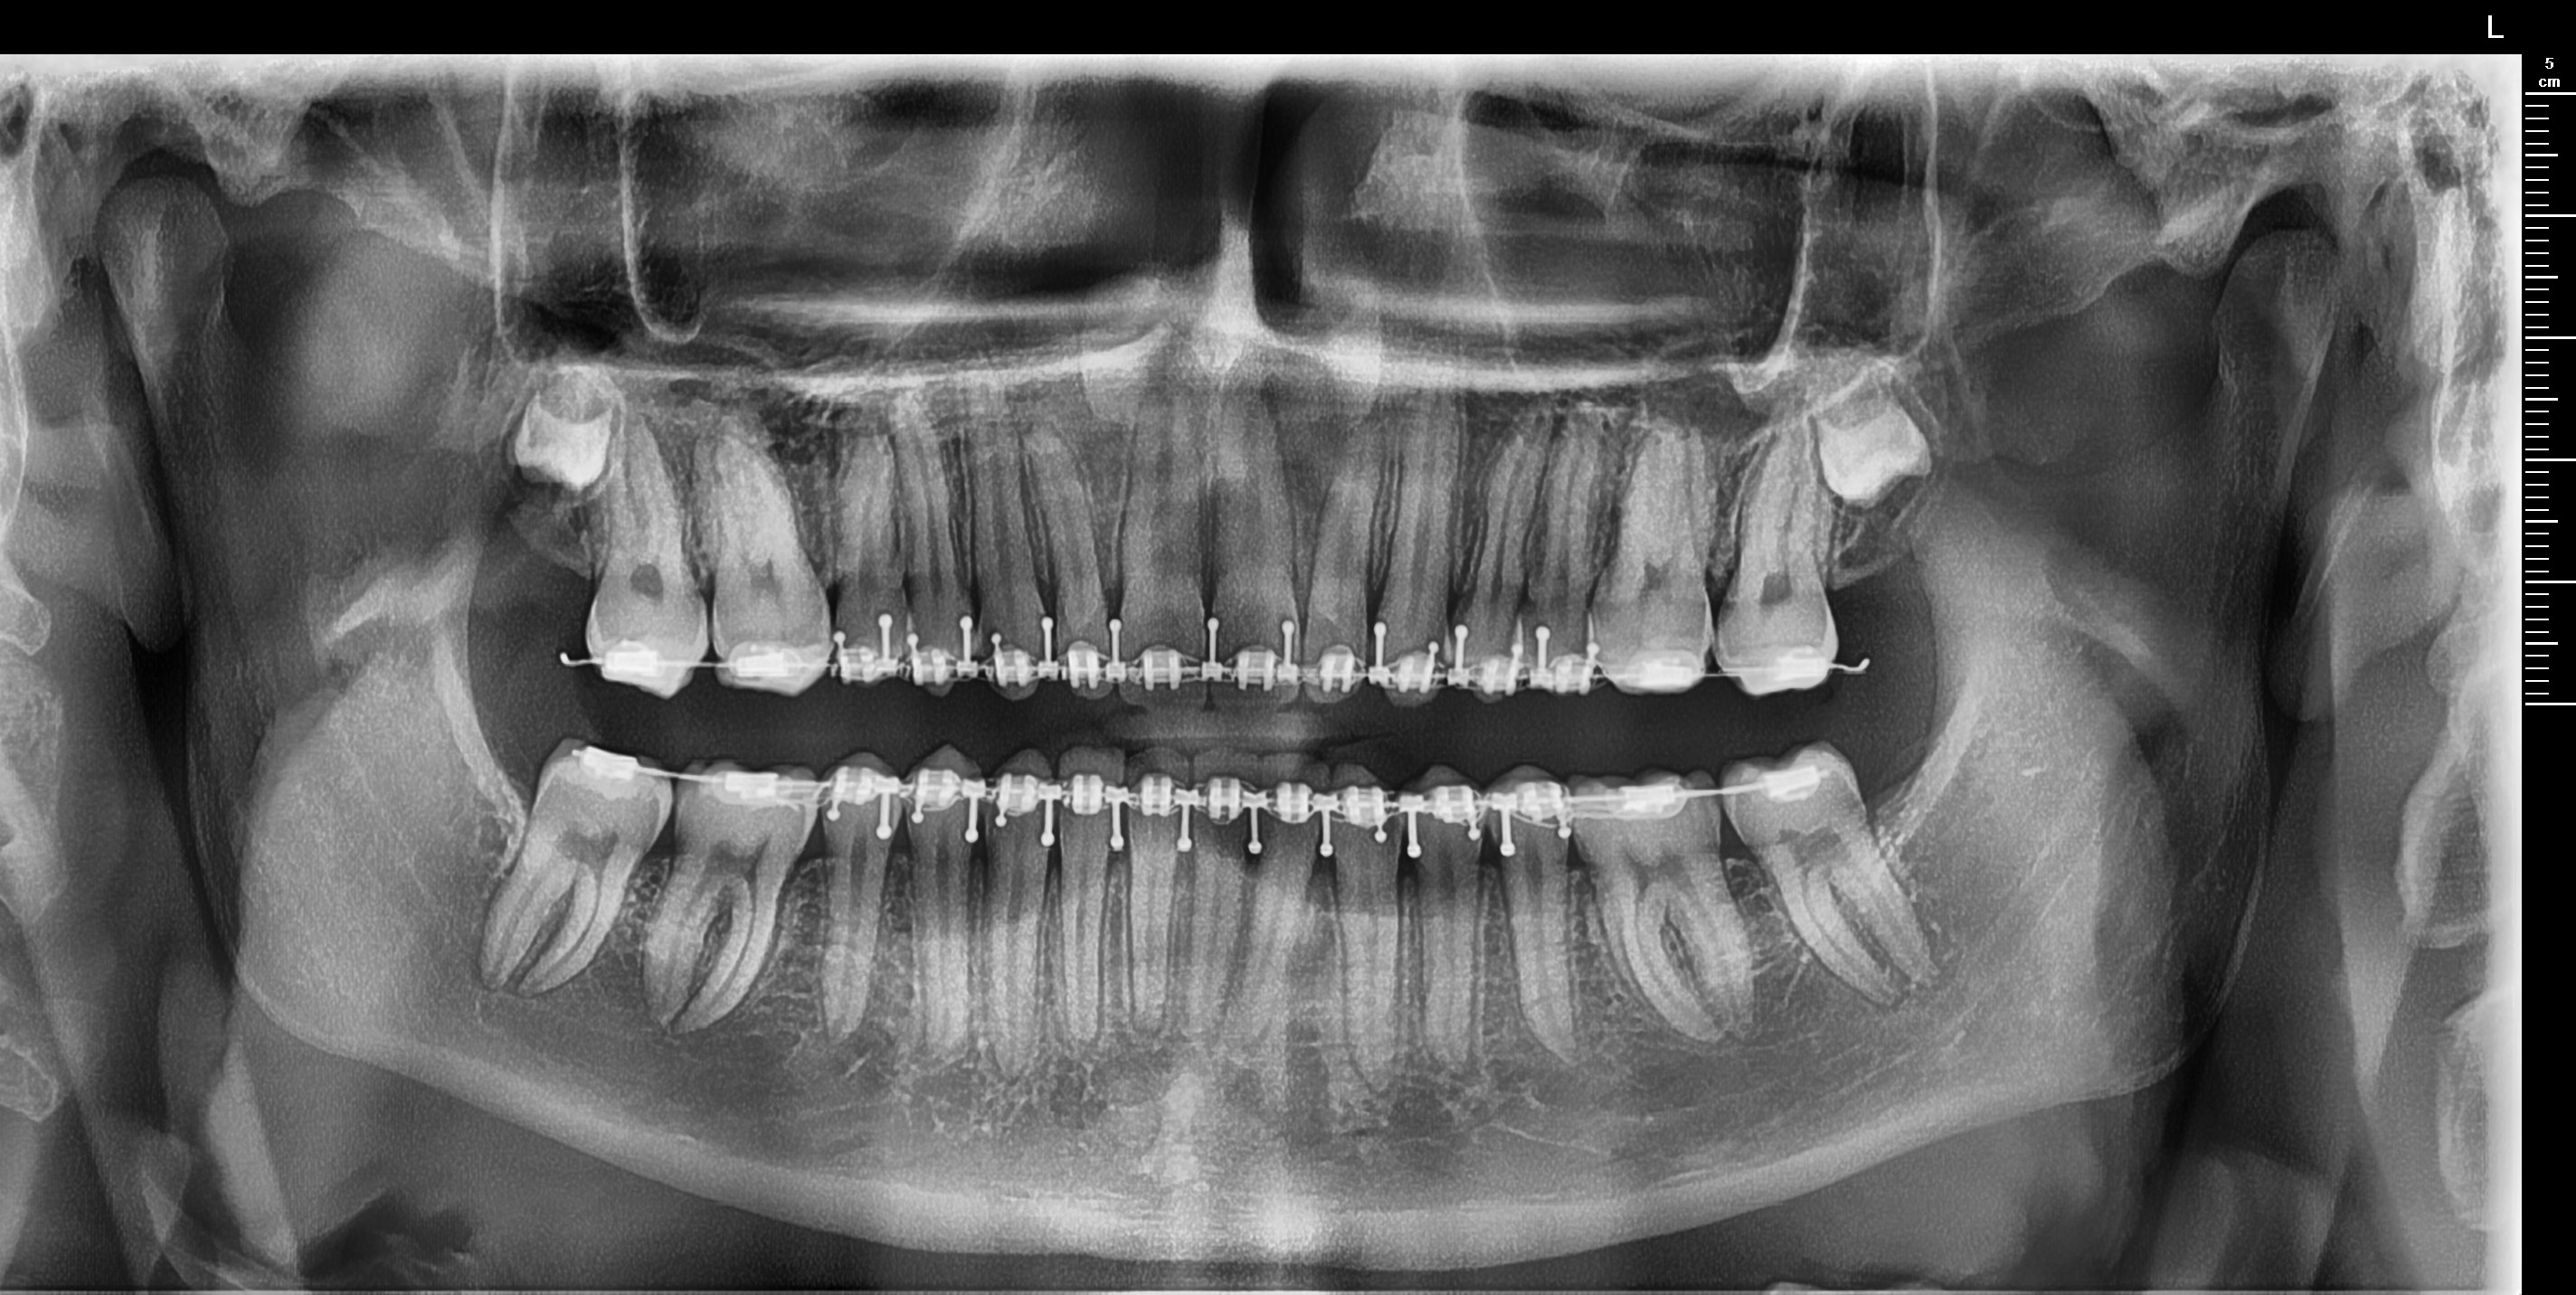

Got a Bimax late september via insurance. These were the movements planned.

LEFORT 1: 2MM ADVANCEMENT

BSSO: 8MM ADVANCEMENT

2° CCW ROTATION

Although post-bimax marpe is rare, I believe I still qualify. my smile is narrow asf and struggle to put my tongue on my the top of my mouth. Finding an orthodontist in the Netherlands willing to provide this is gonna be hard but there are some promising orthodontists im planning to consult. One of these is Aldin Kapetanovic. He has published multiple research papers about marpe and even created his own design: Dutch Maxillary Expansion Device. It contains 4 miniscrews and is 3d printed (picture below). Can those knowledgeable on MARPE DESIGN advise if this is a good design? Would really help me out as i'm not too knowledgeable.